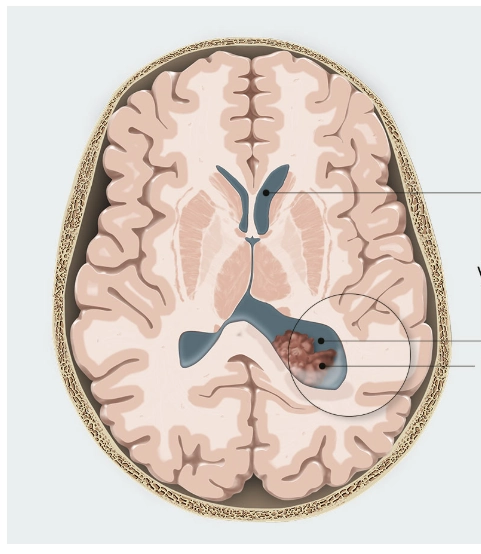

Bệnh xơ cứng củ ở thai nhi (Tuberous Sclerosis Complex - TSC)